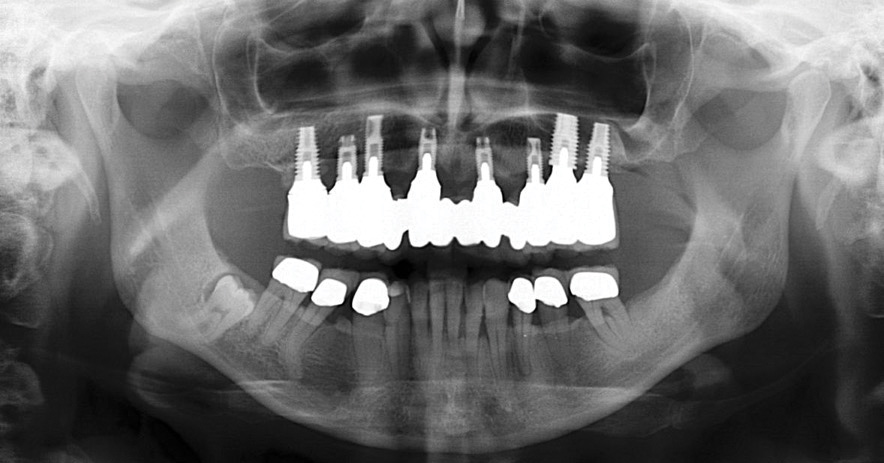

Presence of Zone 1, 2, and 3 Bone

For patients in whom alveolar bone is present in all three zones of the edentulous maxilla, conventional implants may be placed (Figure 5). This should allow for a favorable arch form of anterior, posterior, and possibly intermediate implants for a fixed prosthesis.8,9

Fig 5. Axial implant placement, with presence of bone in zones 1, 2, and 3.

Figure 5